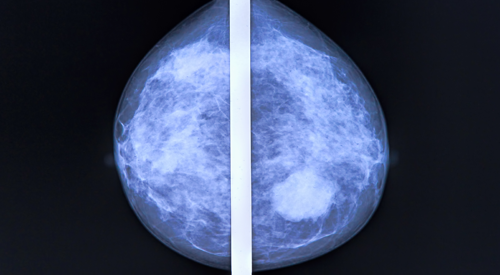

Data recently published in Cancer Cell1 showed a significant uptick in recent cancer screening procedures like mammography, PSA, Papanicolaou test, and low dose CT scan. This increase directly contrasts the low screening rates observed during the first pandemic peak.

Moreover, significant shifts were observed with regard to racial distribution of patients undergoing mammography in period 6, defined as June 2020 to September 2020, and period 7, defined as September 2020 to December 2020, vs 3 months pre-pandemic. Higher proportions of non-Hispanic White patients were noted in these 3 time periods, at 83.2% and 82.0% vs 79.0%, respectively (P < .001). Lower proportions of non-Hispanic Blacks were noted, at 5.2% and 5.3% vs 6.3%, respectively (P < .001), as well was Hispanic/Latino patients, at 2.4% and 2.6% vs 3.3% (P < .001).

The racial disparities were illustrated by reduced numbers of non-Hispanic Black and Hispanic patients undergoing mammography during period 7 (n = 1774 and n = 867, respectively) vs the 3 months before the pandemic (n = 1859 and n = 977, respectively; this contrasted with the increase in mammography tests in the whole group of patients analyzed. This finding was further validated by comparably significant shifts observed during periods 6 and 7 vs other pre-pandemic time periods.

“We identified racial disparities within mammography testing from June to December 2020, with a significant decrease in the proportion of Black and Hispanic patients,” the study authors wrote. “In light of previously established low screening rates in ethnic minorities, these findings are concerning and suggest the pandemic may accentuate racial disparities related to cancer screening.”